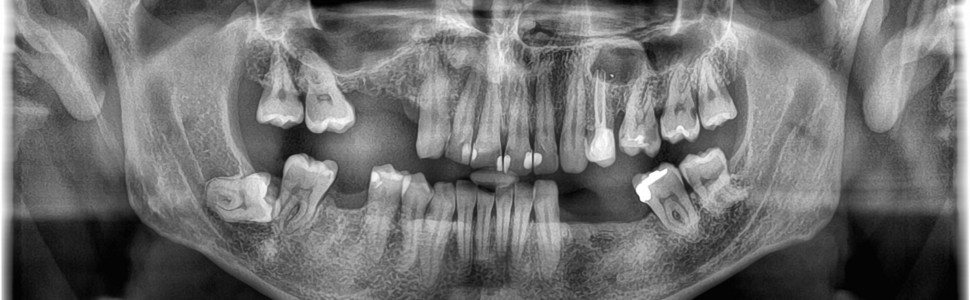

Leczenie zainfekowanej torbieli zęba 24. Trudności diagnostyczne. Rola rentgenodiagnostyki w postawieniu rozpoznania. Opis przypadku

Treatment of infected cyst associated with tooth 24 – case report. Diagnostic difficulties. The role of X-ray diagnosis in making a diagnosis

Torbiel korzeniowa (cystis radicularis) jest najczęściej diagnozowaną torbielą prawdziwą występującą w obrębie kości szczękowych. Jej rozwój jest zazwyczaj powolny i bezobjawowy. Objawy bólowe i obrzęk mogą pojawić się w następstwie zainfekowania torbieli oraz powikłań zapalnych. Celem przedstawionego poniżej opisu przypadku leczenia zainfekowanej torbieli jest zwrócenie uwagi na trudność diagnostyczną torbieli przy współistnieniu objawów zapalnych oraz przydatności diagnostyki radiologicznej w postawieniu prawidłowego rozpoznania i wdrożenia właściwych metod terapeutycznych.

The root cyst (cystis radicularis) is the most commonly diagnosed true cyst occurring in the jaw bones. Its development is usually slow and asymptomatic. Pain symptoms and swelling may appear as a result of infection of the cyst and inflammatory complications. The purpose of the description of the infected cyst treatment presented below is to draw attention to the diagnostic difficulty of the cyst with coexisting inflammatory symptoms and the usefulness of radiological diagnostics in establishing the correct diagnosis and implementing appropriate therapeutic methods.